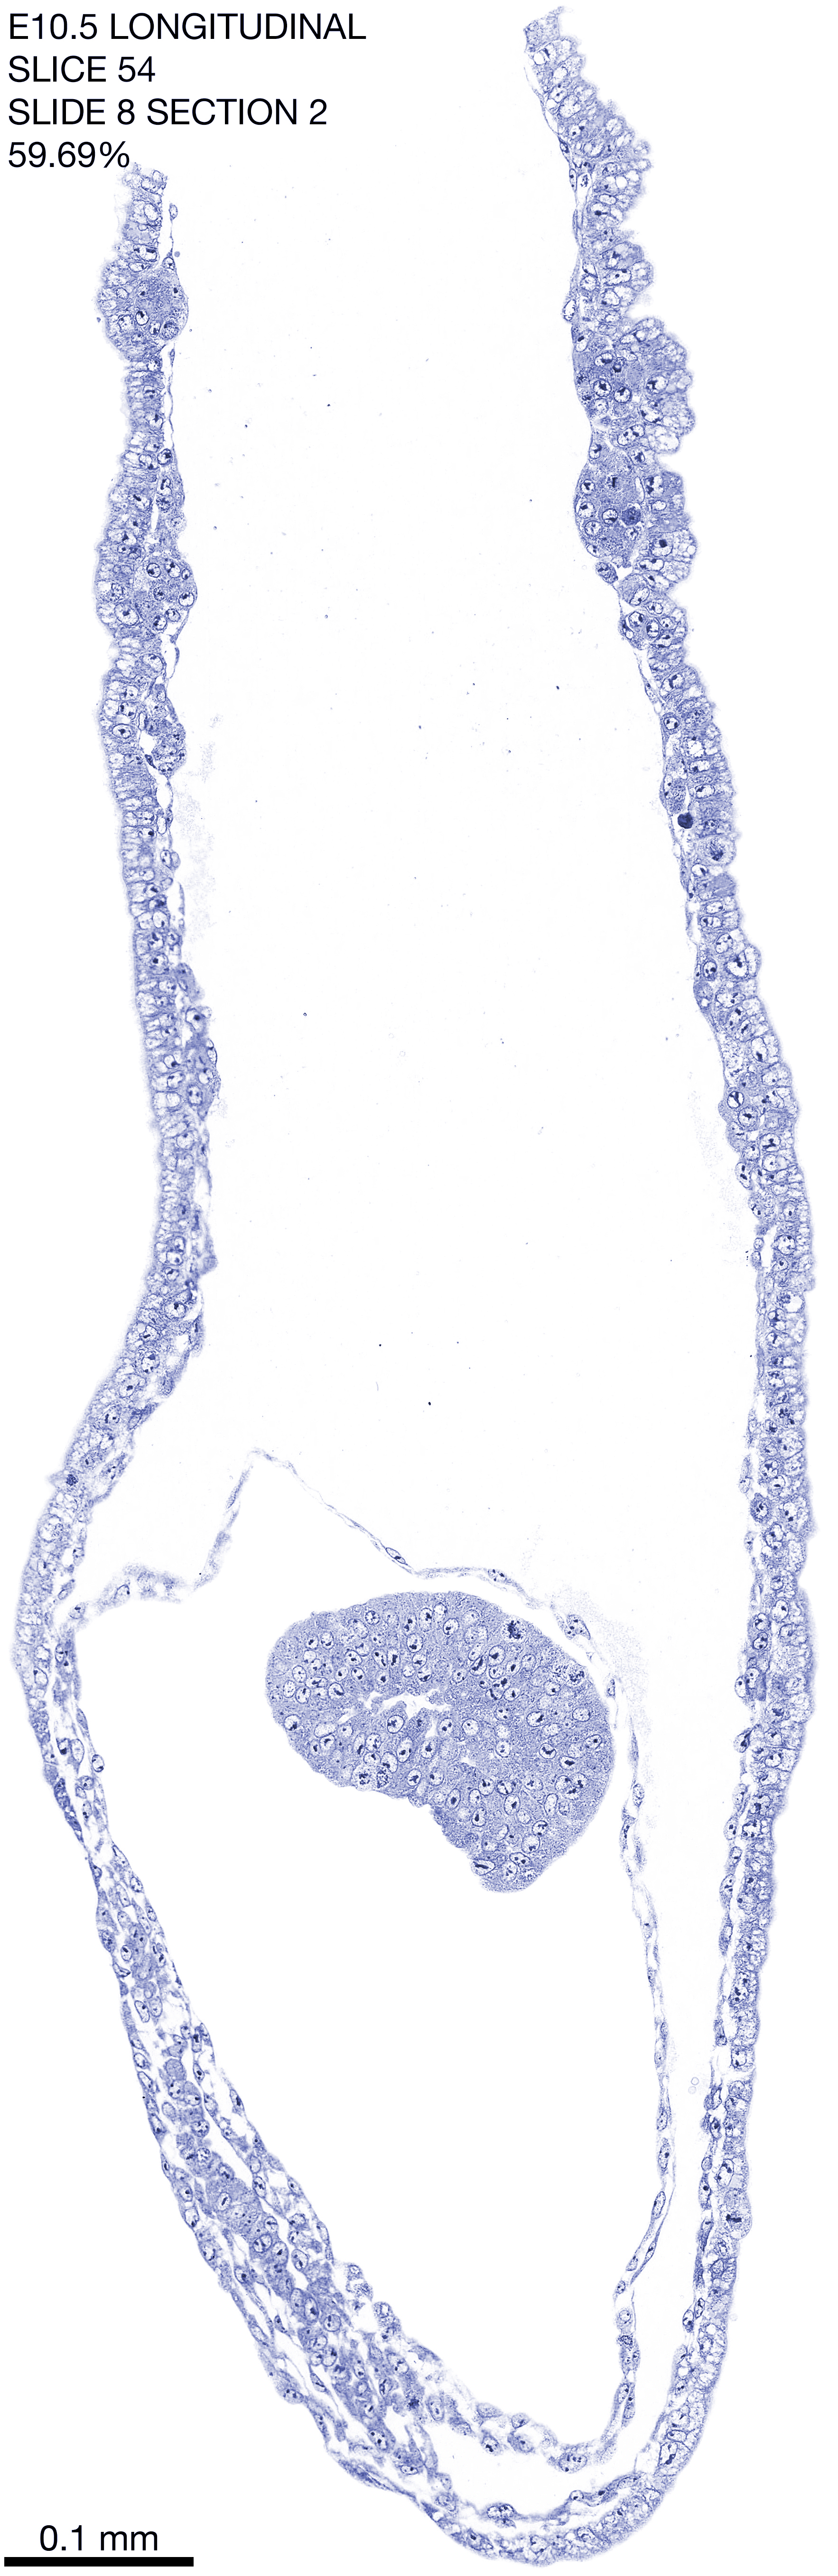

E10.5 Longitudianal Archive This page contains jpg files of ALL SLICES (each 3µm thick) that were scanned of the E10.5 longitudinally cut specimen. Download: Large | High Res Download: Large | High Res Download: Large | High Res Download: Large | High Res Download: Large | High Res Download: Large | High Res Download: Large | High Res Download: Large | High Res Download: Large | High Res Download: Large | High Res Download: Large | High Res Download: Large | High Res Download: Large | High Res Download: Large | High Res Download: Large | High Res Download: Large | High Res Download: Large | High Res Download: Large | High Res Download: Large | High Res Download: Large | High Res Download: Large | High Res Download: Large | High Res Download: Large | High Res Download: Large | High Res Download: Large | High Res Download: Large | High Res Download: Large | High Res Download: Large | High Res Download: Large | High Res Download: Large | High Res Download: Large | High Res Download: Large | High Res Download: Large | High Res Download: Large | High Res Download: Large | High Res Download: Large | High Res Download: Large | High Res Download: Large | High Res Download: Large | High Res Download: Large | High Res Download: Large | High Res Download: Large | High Res Download: Large | High Res Download: Large | High Res Download: Large | High Res Download: Large | High Res Download: Large | High Res Download: Large | High Res Download: Large | High Res Download: Large | High Res Download: Large | High Res Download: Large | High Res Download: Large | High Res Download: Large | High Res Download: Large | High Res Download: Large | High Res Download: Large | High Res Download: Large | High Res